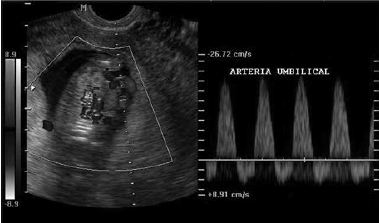

Considere a imagem a seguir:

Assinale a alternativa que indica corretamente o que a imagem representa e seu possível significado.

Diástole reversa / alta resistência na circulação fetoplacentária aliada a possível falência cardiocirculatória fetal.